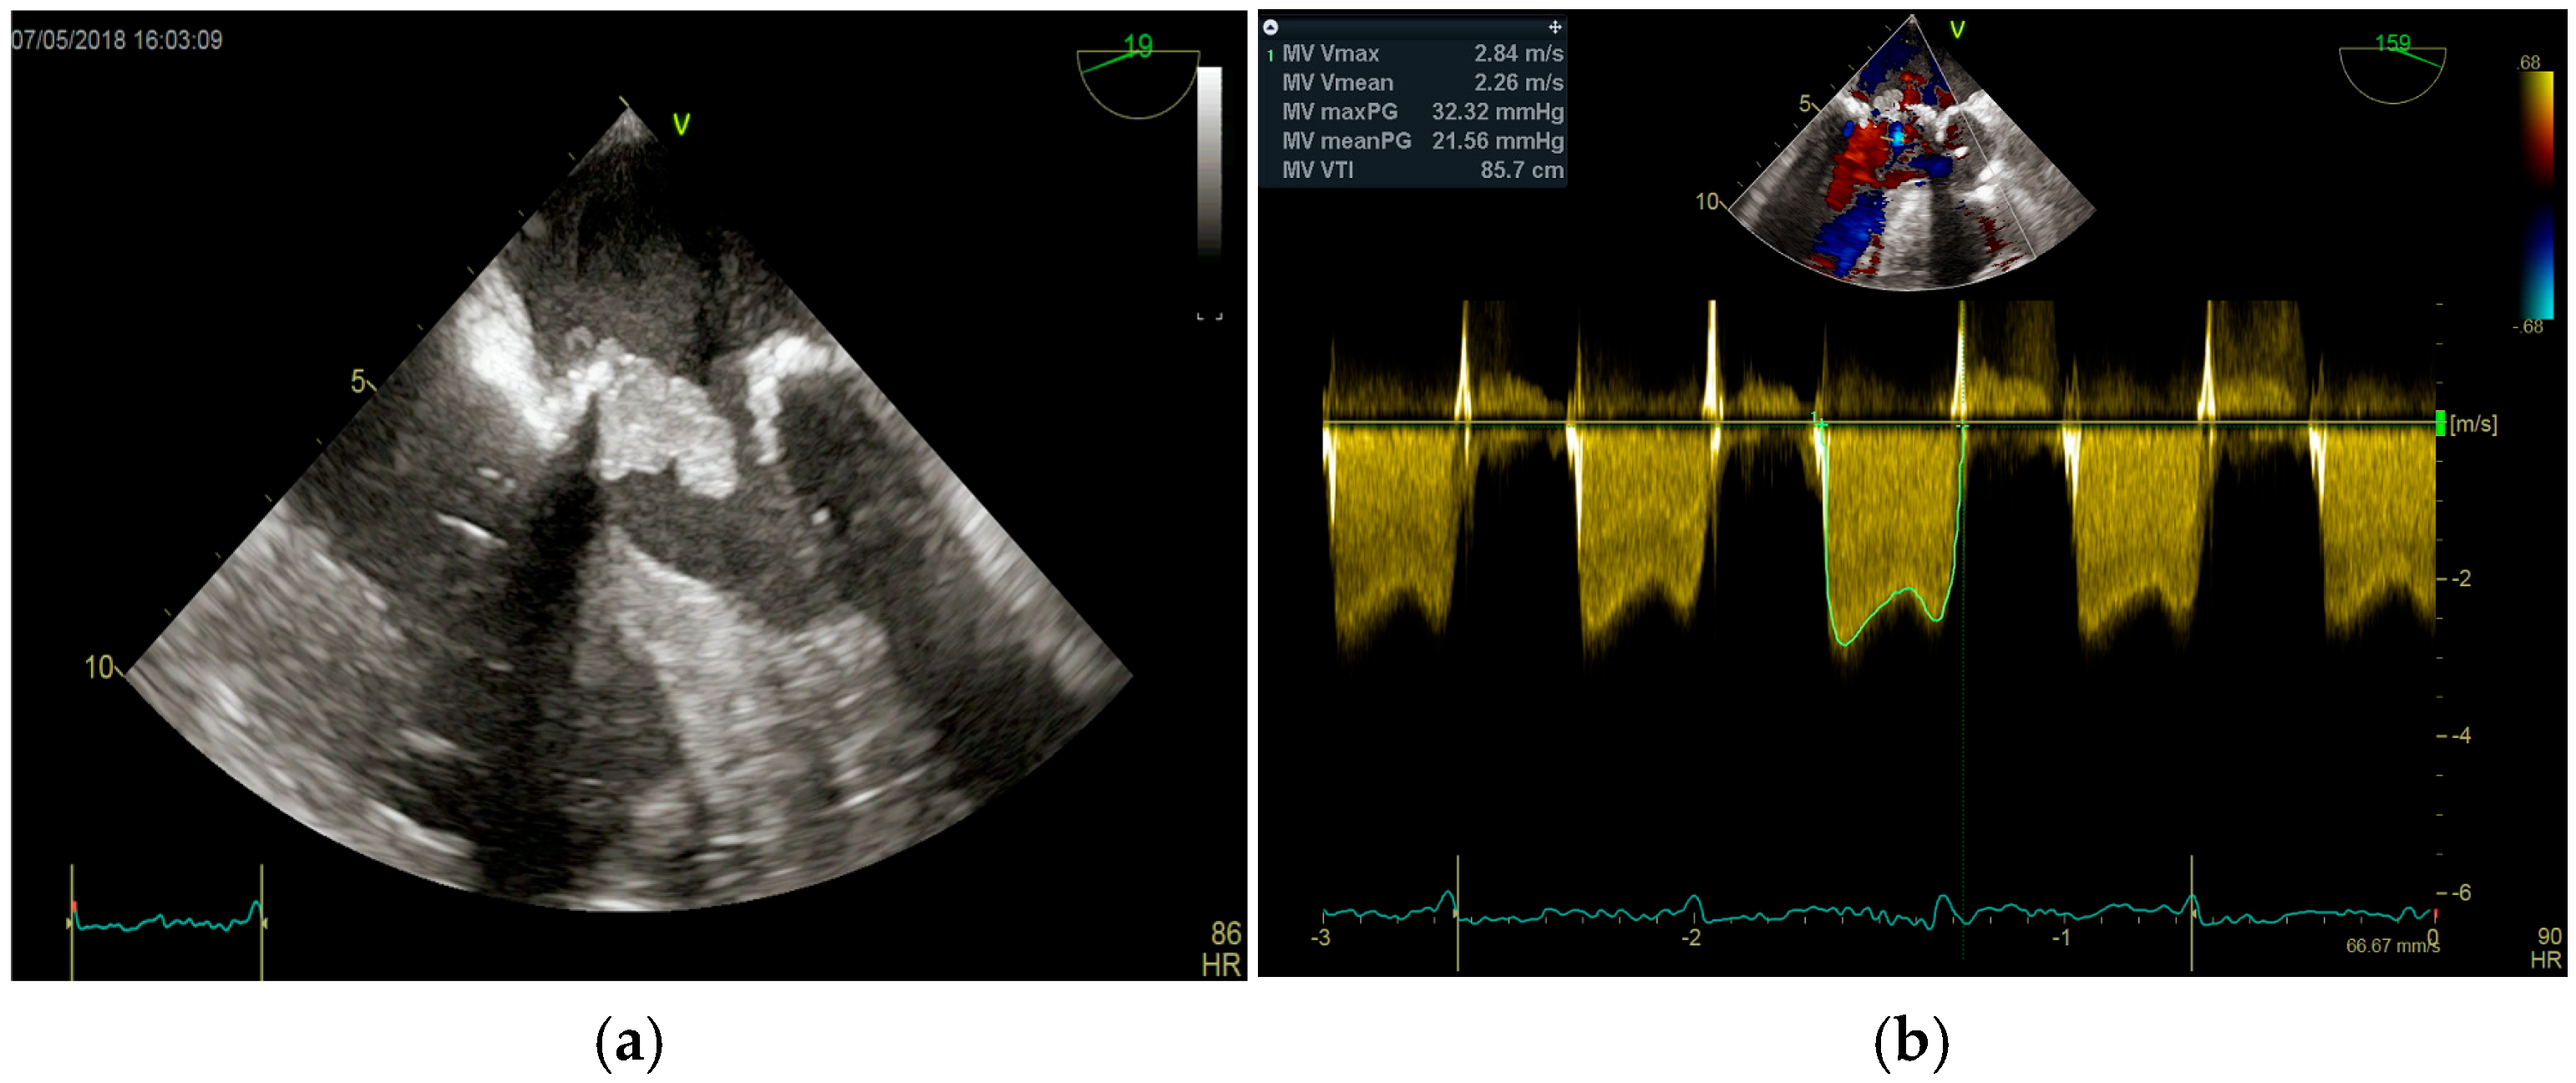

4. Echocardiography

- Echocardiography: As the cornerstone of diagnosis, echocardiography’s limitations in the setting of prosthetic material and operator dependence are well-known. The presence of sewing ring and stent frame shadowing can obscure critical findings, and Doppler flow malalignment may lead to underestimation of prosthetic valve gradients and regurgitation severity [37,58].